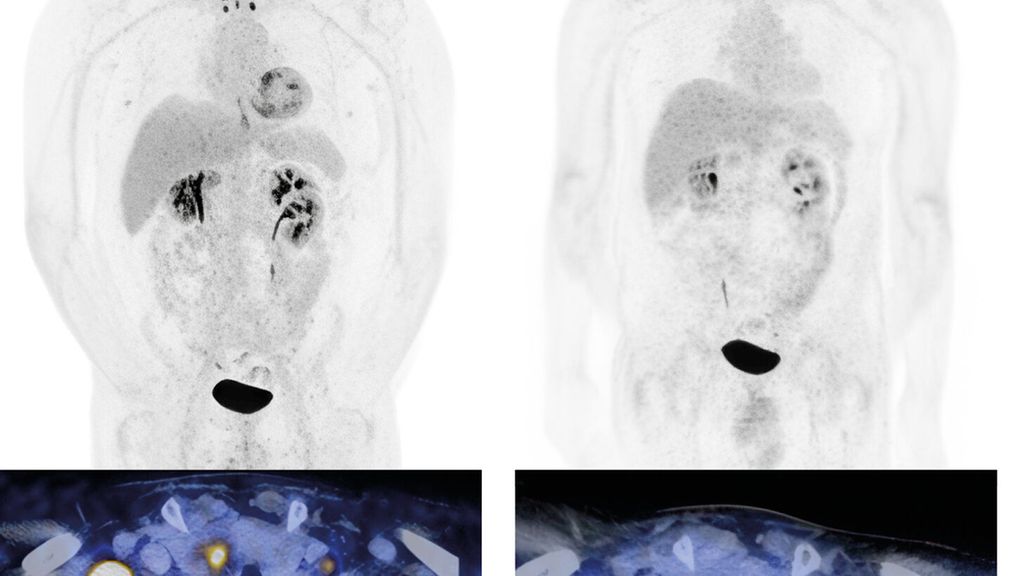

Abb. 1: Urothelkarzinom der Harnblase (initial cT3 cN3 cM0) mit metachron aufgetretener lymphogener Metastasierung. Staging mittels Computertomografie (PET-CT) mit Diagnose der lymphogenen Metastasierung (a, links). Erstes Restaging zwei Monate nach Therapiebeginn mit EV+P (b, rechts). Bildmorphologisch zeigt sich eine Komplettremission. Der Patient befindet sich weiterhin in anhaltender Remission. Bilder und Patient USZ Zürich

Das mediane OS konnte mit dieser Kombination signifikant auf knapp 34 Monate im Vergleich zu 16 Monaten mit alleiniger platinhaltiger Chemotherapie ± IO-Erhaltung gesteigert werden. In der Studie waren auch Patient:innen mit schlechterem Allgemeinzustand (bis ECOG 2) und Patient:innen mit reduzierter Nierenfunktion (GFR ≥30ml/min) eingeschlossen. Ein Update mit einem Follow-up von nun 2,5 Jahren zeigt, dass die Patient:innen, die eine komplette Remission (CR) erzielen, auch längerfristig in einer CR bleiben.6